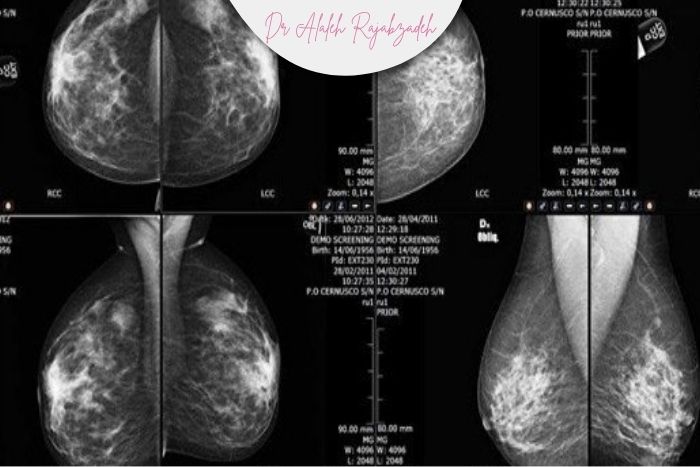

در ماموگرافی تصاویر متراکمتر و سفیدتر دیده میشود.

تودههای ریز ممکن است پشت این تراکم پنهان شوند و تشخیص سختتر شود.

سونوگرافی برای این گروه سنی معمولاً دقت بیشتری دارد.